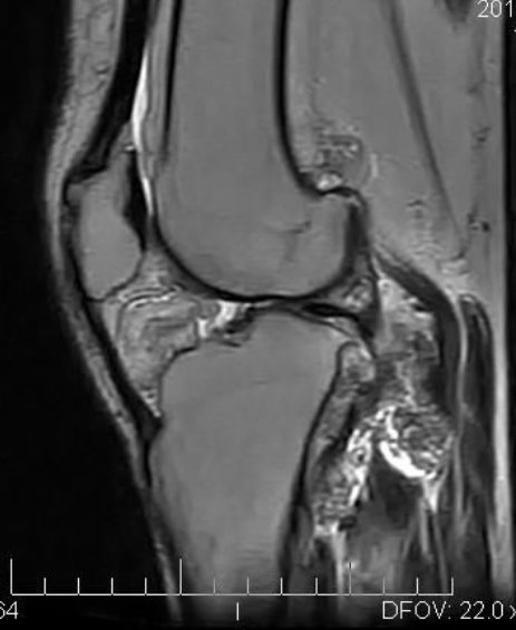

T1